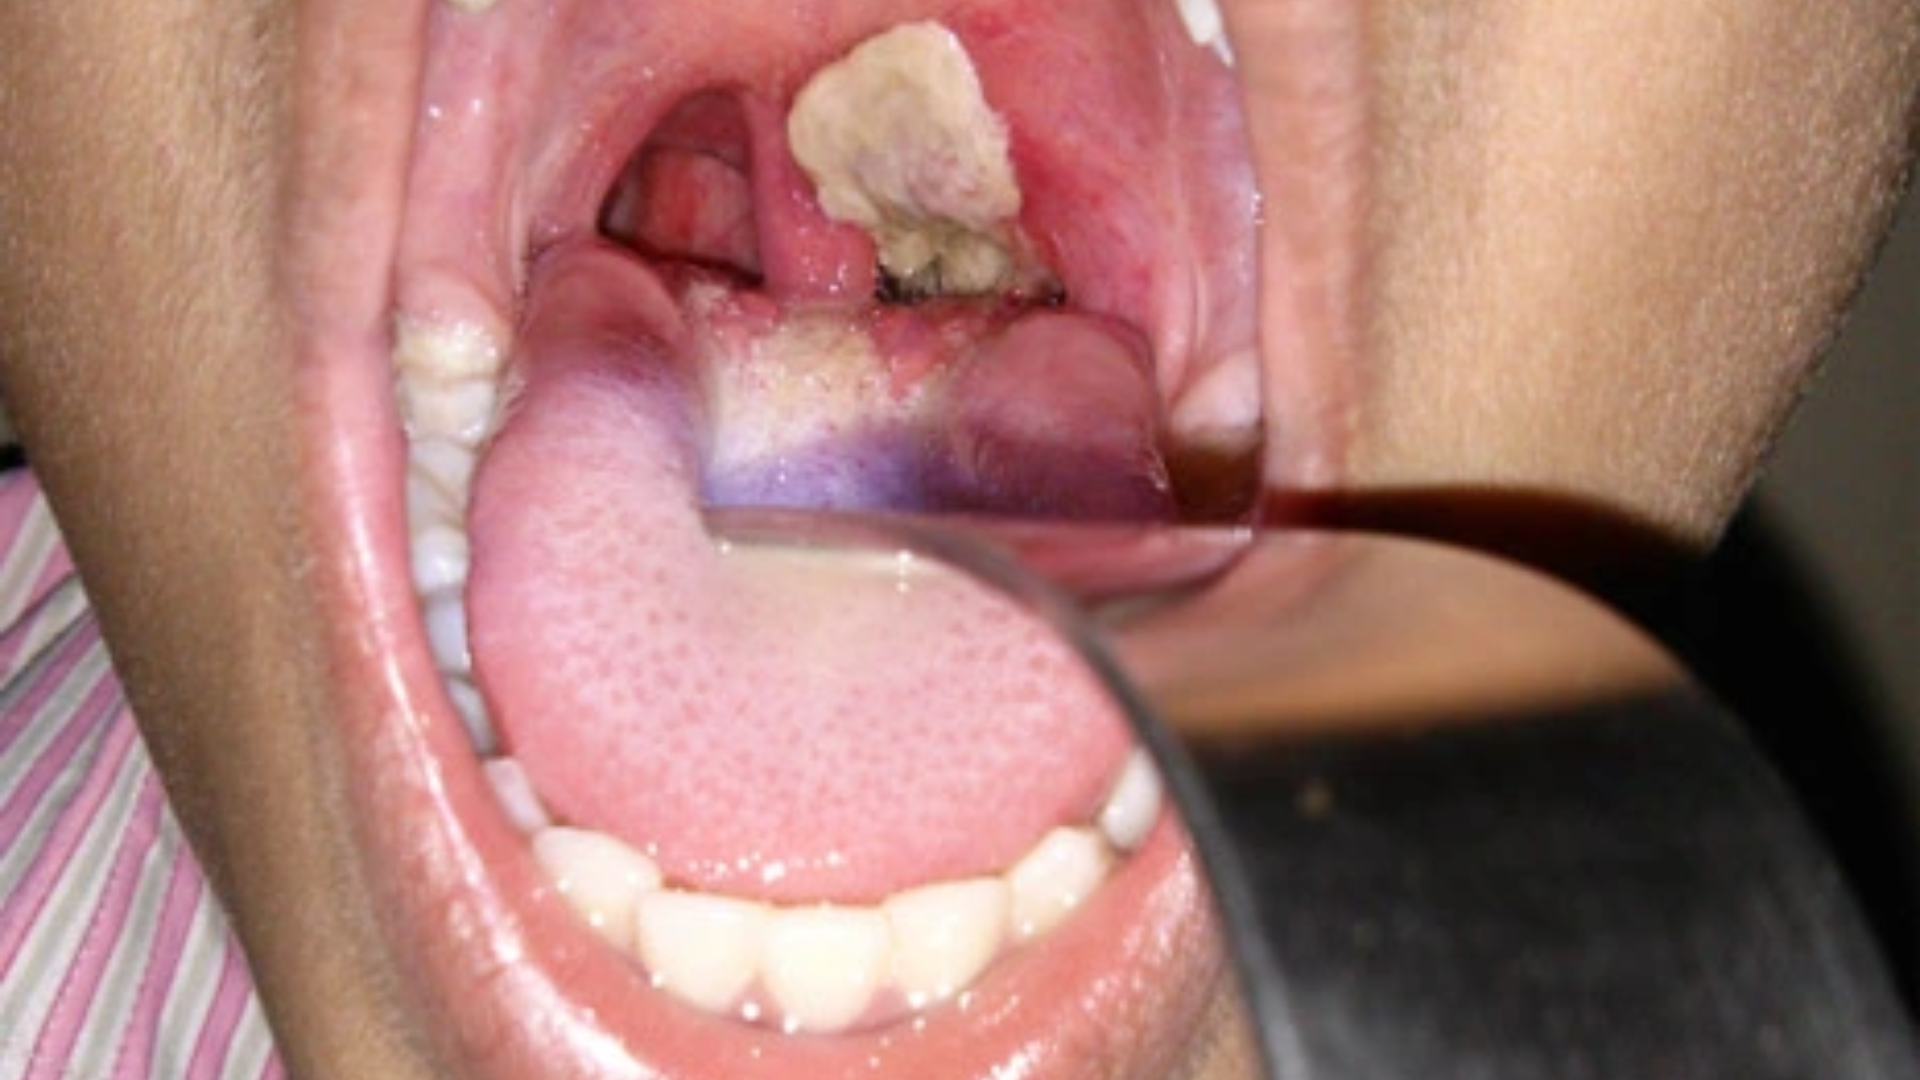

Giai đoạn toàn phát là giai đoạn đặc trưng và có giá trị chẩn đoán nhất của bệnh bạch hầu. Lúc này, tại vùng họng, amidan hoặc thanh quản xuất hiện giả mạc màu trắng xám hoặc xám bẩn, dày, dai và dính chặt vào niêm mạc bên dưới. Khi cố gắng bóc giả mạc, bề mặt niêm mạc dễ chảy máu, đây là dấu hiệu giúp phân biệt với các mảng giả mạc trong viêm họng thông thường.

Các triệu chứng toàn thân thường không rõ rệt, sốt chỉ ở mức nhẹ đến vừa và không tương xứng với tổn thương tại chỗ. Người bệnh có thể xuất hiện hơi thở hôi, đau họng ngày càng tăng, nuốt khó, kèm theo giọng mũi hoặc khàn tiếng nếu tổn thương lan xuống thanh quản.